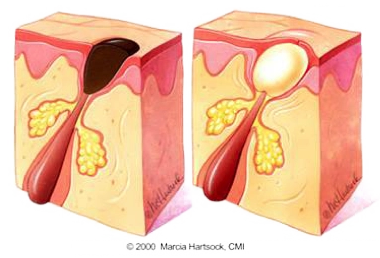

Comedones & Enlarged Pores

Open Comedones (Blackheads) The characteristic black hue of these comedones isn't a sign of embedded dirt or grime. Instead, it's the result of oxidation reactions when the trapped oil and skin cells are exposed to the air.

Closed Open (Whiteheads) are pores that are completely sealed with a thin layer of skin, unlike blackheads. This seal stops oxidation, causing small, light-colored bumps that may feel slightly raised.